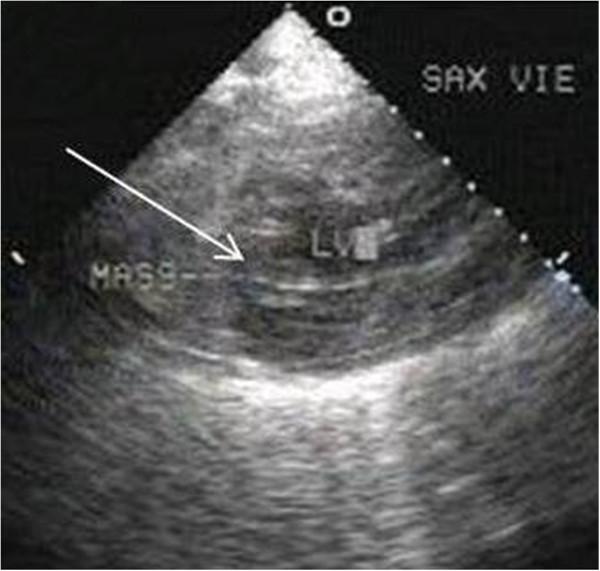

Metastatic involvement of the heart is a rare occurrence and remains undiagnosed until autopsy. In some instances, patients may have cardiac symptoms, leading to ante-mortem diagnosis. Although most primary cancers have been documented to metastasize to heart, the existing literature on cancers of upper aero-digestive tract is an exception, with only a few reports. We report four cases of upper aero-digestive tract cancers, three of which arise from oral cavity, one from lower esophagus, metastasising to the myocardium, detected on 18 F - Fluoro-deoxy-glucose Positron Emission Tomography/Computed Tomography (FDG PET/CT) study , in the absence of related symptoms.

心脏转移受累较为罕见,直至尸检时才得以诊断。在某些情况下,患者可能会出现心脏症状,从而得以生前诊断。尽管大多数原发性癌症都有转移至心脏的记录,但关于上消化道癌症的现有文献却是个例外,仅有少数报道。我们报告了4例上消化道癌症,其中3例起源于口腔,1例起源于食管下段,在没有相关症状的情况下,经18F-氟脱氧葡萄糖正电子发射断层扫描/计算机断层扫描(FDG PET/CT)检查发现转移至心肌。